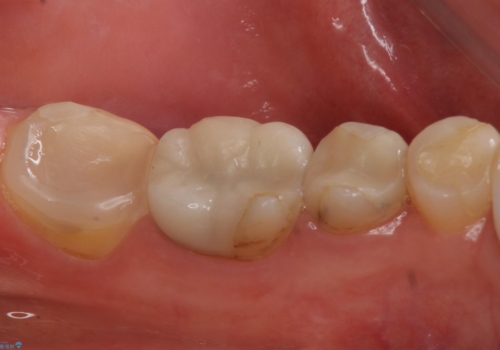

3. 昔いれたクラウンが割れたので金属の被せ物を入れたいの治療後